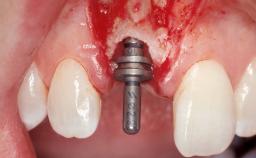

| Placement Protocol | Immediate implant placement |

| Tooth Site | Maxillary incisor or canine |

| Socket Morphology | Single-root socket |

| Socket Integrity | Damage to one or more bone walls |

| Bone Volume | Damage to one or more socket walls |